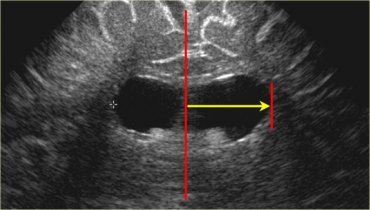

Measurement of the ventricular system needs to be performed on a symmetrical, easily reproducible view. The ventriculo-cranial ratio (VCR) is the ratio of distance between the lateral sides of the ventricles and the biparietal diameter. This is usually expressed as a percentage with a normal value of around 33-36% in a preterm infant. This value is of most use in monitoring the degree of change between successive measurements. An increasing VCR should trigger frequent reassessments with measurements of the cerebral resistive index (see below).

The Ventricular index, as described by Levine, is the absolute distance between the falx and the lateral wall of the anterior horn in the coronal plane at the level of the third ventricle. Values more than 4mm above the 97th centile for gestational age are indicative of significant ventricular dilatation (see chart). A study by Brouwer et al compared early CSF drainage, at a ventricular index of 4 mm above the 97th centile, to drainage beyond this threshold, and showed that early treatment was associated with better development quotient at 2 years and a decreased likelihood of shunt dependence; there was, however, no reduction in the rate of cerebral palsy with early drainage.